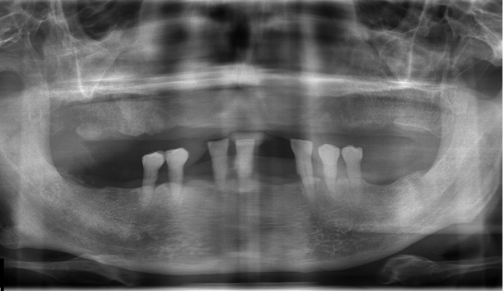

전체 임플란트 Before&After

• 2016.08.23 - 2016.09.04 - 2020.06.17

Before

After

After 4년 뒤